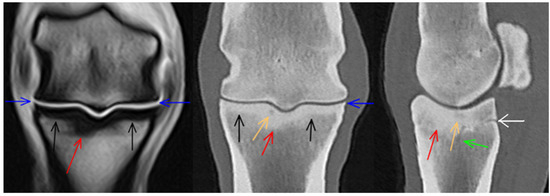

3.2. Proximal Phalanx